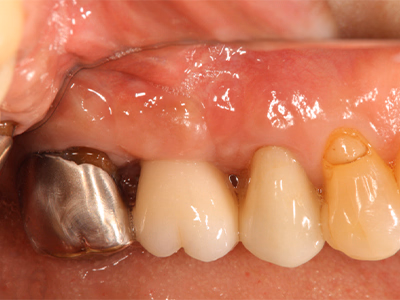

治療前

右下奥歯で咬むと違和感がある/歯ぐきが腫れてきた

治療内容

- ① 顕微鏡視下根管治療(マイクロエンド)

- ② 根管拡大・洗浄2回

- ③ 2ヶ月経過観察で再生反応確認後に根管充填

- ④ マイクロスコープ下でファイバーコア築造+セラミック冠装着

約3ヶ月半(1回の治療:1~2時間)

- マイクロエンド132,000円

- ファイバーコア 22,000円

- 仮歯 6,600円

- セラミック冠 165,000円

- 術後の腫れ・痛み・出血

- 慢性根尖性歯周炎が再発する可能性

- 定期的なチェックが必要

サイナストラクトは消失し、CTでも透過像の改善を確認。

術後数日で痛み消失し、セラミック装着後も良好な咀嚼が可能。

現在は年1 回の定期チェックを継続中。